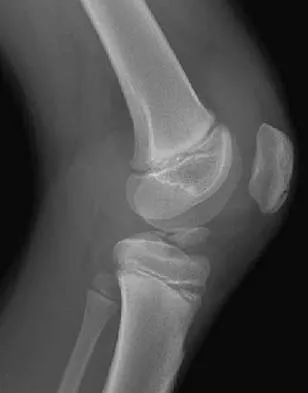

Figure 31 shows the AP and lateral radiographs of the elbow of a 56-year-old man with chronic polyarticular rheumatoid arthritis. His function continues to be limited by pain with activities of daily living. Examination shows that his total arc of motion is 110 degrees. Nonsurgical management has failed to provide relief. Treatment should now consist of

A semiconstrained prosthesis can provide excellent results in carefully selected patients. Because the radiographs show extensive joint destruction with loss of the capitellum and trochlea, a capitellocondylar total elbow (unconstrained) prosthesis is contraindicated. Elbow fusion is poorly accepted, and the radiographs show too much articular destruction for a radial head excision, synovectomy, or interposition arthroplasty to be effective. Ewald FC, Simmons ED Jr, Sullivan JA, et al: Capitellocondylar total elbow replacement in rheumatoid arthritis: Long-term results. J Bone Joint Surg Am 1993;75:498-507.